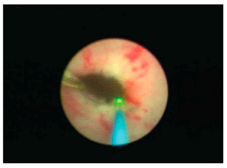

Estenosis de uréter:

La estenosis de uréter consiste en un estrechamiento en el uréter, el cual es un conducto que comunica el riñón con la vejiga. Según la localización y longitud de la misma esta puede ser tratada de forma efectiva mediante abordaje endoscópico para la apertura de la estenosis con láser.